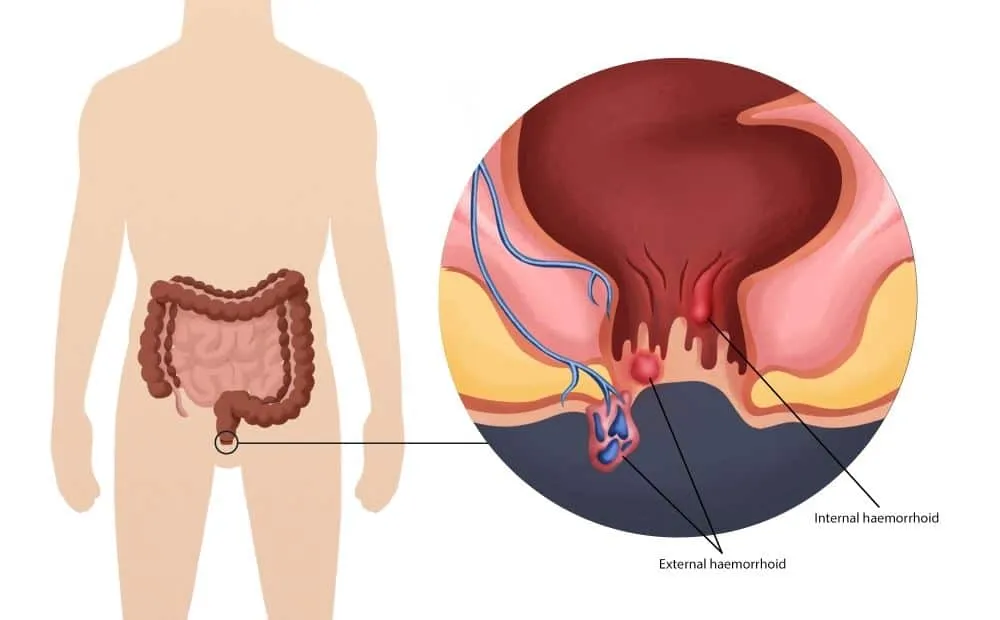

An anorectal abscess is a painful collection of pus near ...

Seeing blood during passing stool can be frightening ...

ਬਵਾਸੀਰ (ਹੈਮੋਰਾਇਡਸ) ਗੁਦਾ ਅਤੇ ਮਲਦਵਾਰ ਦੀਆਂ ਸੋਜੀ ਹੋਈਆਂ ਰਗਾਂ ਹਨ ...